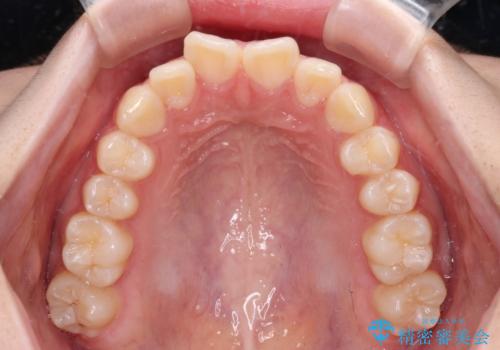

- 上下前歯のねじれを気にして来院された患者様です。

ワイヤー矯正でもマウスピース矯正でも対応可能でしたが、マウスピース矯正の自己管理が面倒であること、上顎前歯の捻転が著しいことから、ワイヤー矯正での治療を希望されました。